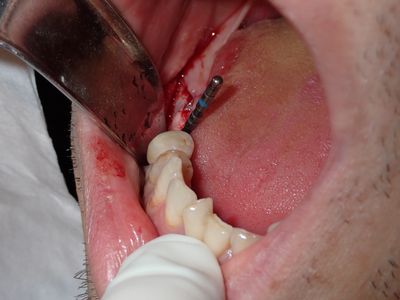

relatively straight forward implant placement, some bone expansion and countersinking. buccal bone thin, grafted with sticky bone from allograft folloewd by collagen mmebrane soaked in prf fluid, additional fibrin membrane used